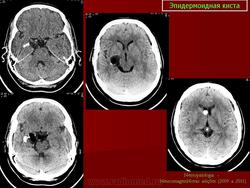

Эпидермоидная киста